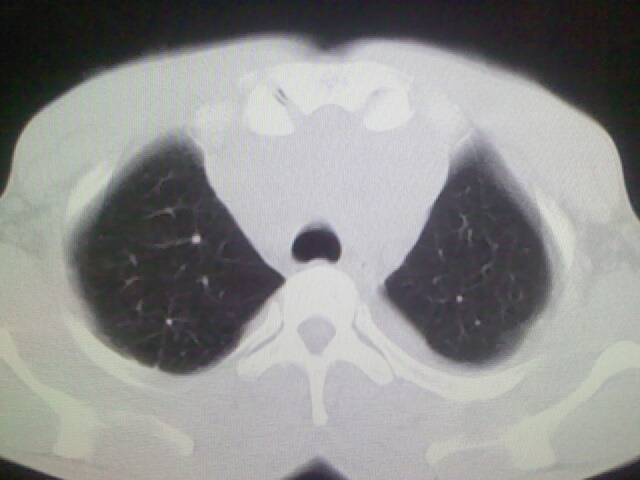

以下是引用杀毒软件在2008-9-3 6:11:00的发言:[br]侵袭性胸腺瘤------一般不侵到气管旁[br][br]考虑----纵隔淋巴瘤,心包及胸膜受累

以下是引用随光逐影在2008-9-3 7:07:00的发言:[br]1)考虑淋巴瘤可能。2)双侧胸腔积液(以左侧为甚)。3)心包积液。